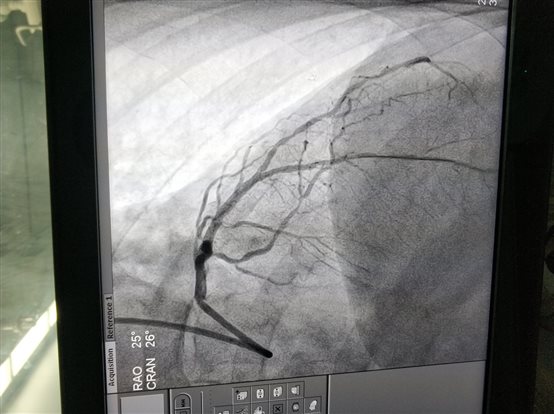

2018年7月4日上午中西医结合医院心内科又成功进行了一例冠脉支架植入术,此患者女性67岁,反复胸闷胸痛,活动后加重,冠脉造影提示前降支近中段严重狭窄95%,经介入治疗后前降支串联植入美敦力支架两枚,狭窄解除,血管通畅,患者症状解除,生活质量恢复。中西医结合医院心内科自2016年起即获得了上海市冠状动脉内治疗介入准入,有资质开展一系列治疗。并且上海的医保覆盖患者可以享受和其他医院一样的优惠支付政策。